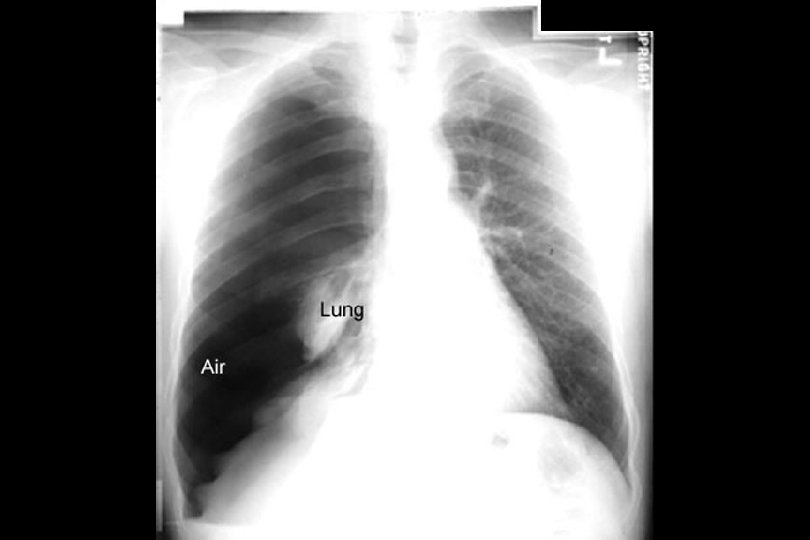

Pneumothorax Relaxation atelectasis Hydro-pneumo Large right hemithorax